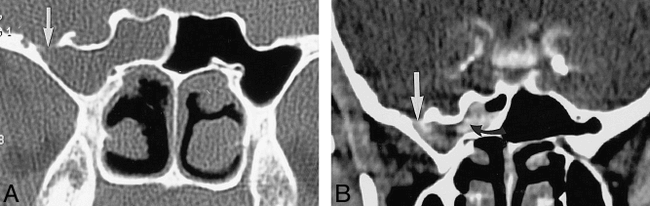

Two patients with bone defects on high-resolution CT and normal results of radionuclide cisternography and CT cisternography.

A, Coronal CT scan shows a defect (arrow) in the right cribriform plate with adjacent mucosal thickening.

B, Coronal CT scan of the temporal bone shows a large defect (arrow) in the tegmen mastoideum and mucosal thickening in the postsurgical mastoid bowl. No contrast accumulation is seen in the mastoid defect. Surgery confirmed the defect and leak in this patient.